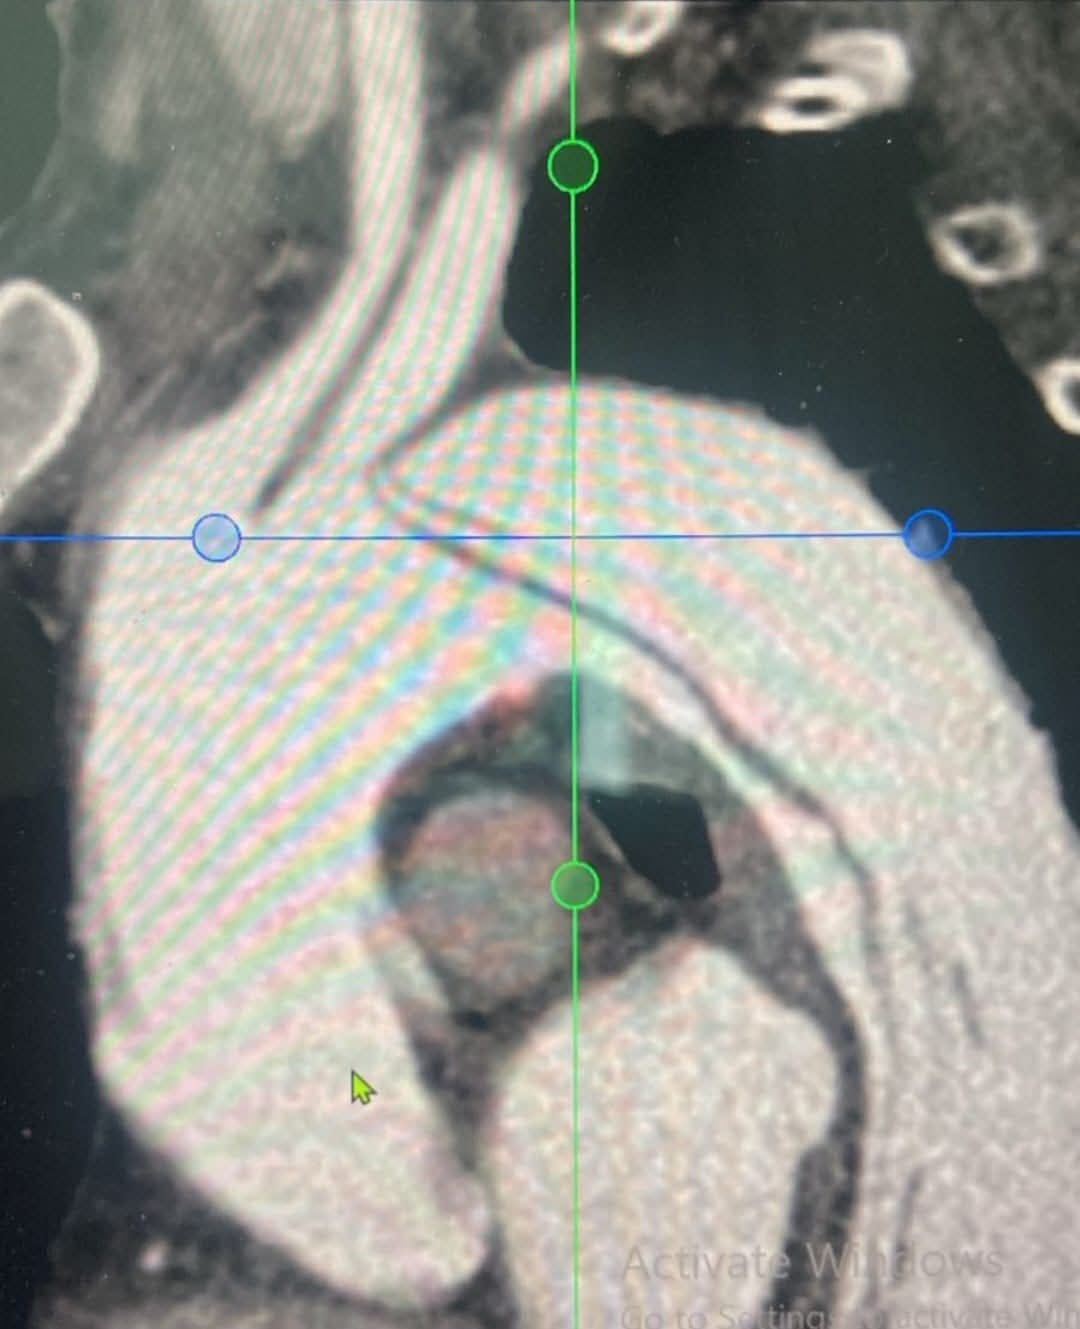

وقد تمت العملية بدقة عالية على مدار يومين بإشراف دكتورة/ غادة ماهر، النائب الطبي، ودكتور/ عبداللطيف الجيار، رئيس قطاع القاهرة؛ حيث قاد الأستاذ الدكتور/ عاطف عبد الحميد الفريق الطبي لإجراء جراحة توصيل الشريان السباتي بالرقبة أولاً، ثم تركيب الدعامات المغطاة لغلق التمدد الشرياني في اليوم التالي، بمعاونة متميزة من أطقم التخدير والرعاية المركزة والتمريض.